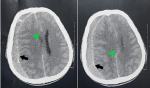

Diagnostic assessment: emergency CT scan of the head showed an isodense right hemispheric subdural collection with mass effect on the right lateral ventricle and midline shift (Figure 1).

Diagnosis: imaging findings were consistent with a subacute subdural hematoma.

Figure 1: preoperative CT scan of the head in axial planes